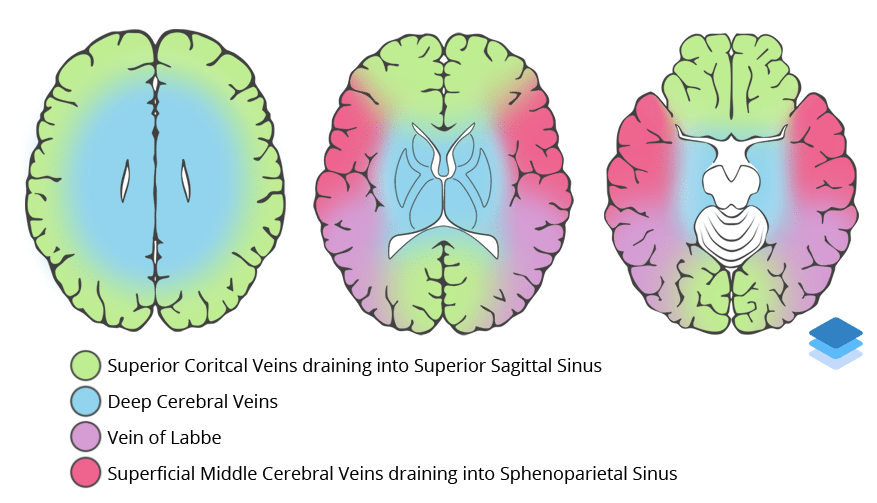

Venous Sinuses.

Approximations of venous vascular territories of the brain.